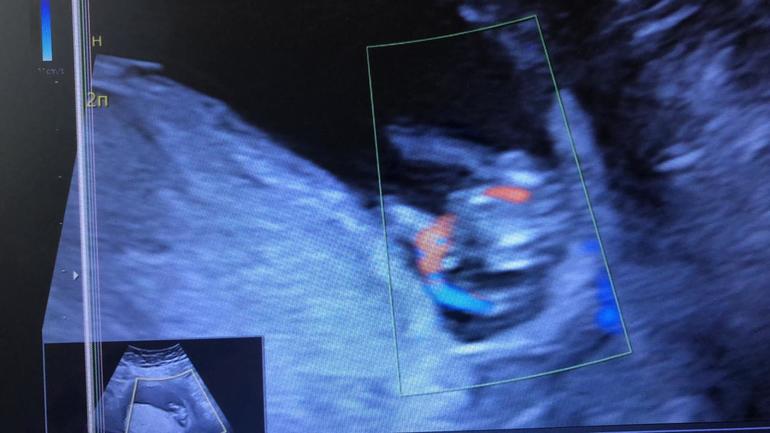

Первый скрининг. Кто там?🙈

Беременность- 1 триместр ( только до 10 недель)Есть предположения по фото?😅

Фото 1 это дали на узи, а третье-это скрин видео. Как бы снизу😅попу снимали. Ножки влево уходят.